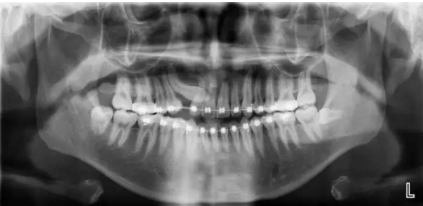

阻生齒外科聯(lián)合正畸治療

24.png

25.png

26.png

27.png

28.png